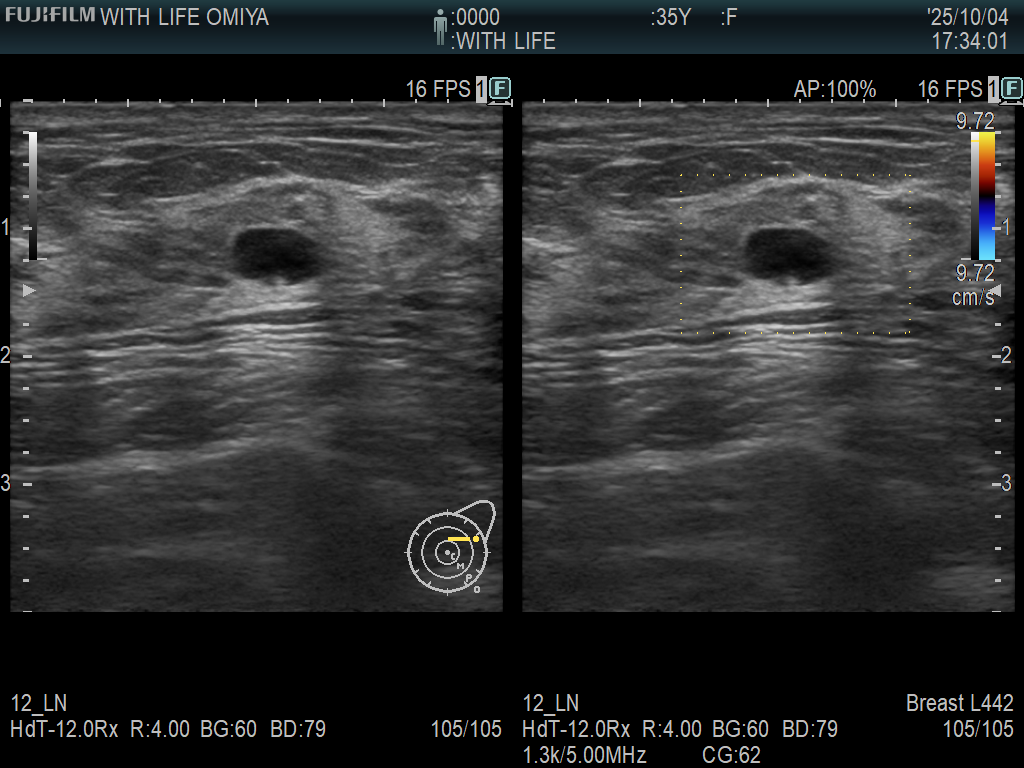

当院では最新の 3Dマンモグラフィ(トモシンセシス) を導入しており、従来のマンモグラフィ画像(2D)に比べて乳腺の重なりを分離して表示できるため、小さな病変や見えにくい部分も評価しやすくなります。(左が3D, 右が2D)

2Dマンモグラフィと3Dマンモグラフィの比較

項目 2Dマンモグラフィ 3Dマンモグラフィ(トモシンセシス)

撮影方法 乳房を圧迫して2方向(上下・斜め)から平面画像を撮影 乳房を圧迫し、X線の管球が移動して乳房を多方向から複数枚撮影→断層画像を再構成(3D)

画像の特徴 平面的な1枚画像で、乳腺や病変が重なって写ることがある 1mmごとのスライス画像で乳腺重なりを分離し、立体的に観察できる

検出精度 高濃度乳腺では病変が隠れることがある 高濃度乳腺でも腫瘤・石灰化をより明瞭に描出できる

メリット ・被ばく線量が少ない ・乳腺の重なりによる見落としが減少

・乳がん検診の標準検査 ・がんの早期発見率が向上

・撮影・読影が比較的短時間 ・再撮影(要再検)の減少につながる

デメリット ・乳腺の重なりで異常を見落とす可能性 ・2Dより被ばく線量がやや多い(約1.2〜1.5倍)

・要再検が出やすい ・読影時間が長くなる傾向

適している方 ・一般的な検診目的の方 ・高濃度乳腺の方

・乳腺が比較的少ない方(40歳以上の方) ・過去に要再検となった方

・乳がん検診を1度も受けたことのない方 ・より精度の高い検査を希望する方

検査時間 約5~10分 約10~15分(撮影枚数が多いため)

被ばく量 低い(基準内) やや高いが、基準内で安全性は確保されている

費用(自費の場合) 相場3千~8千円 相場1万~2万円